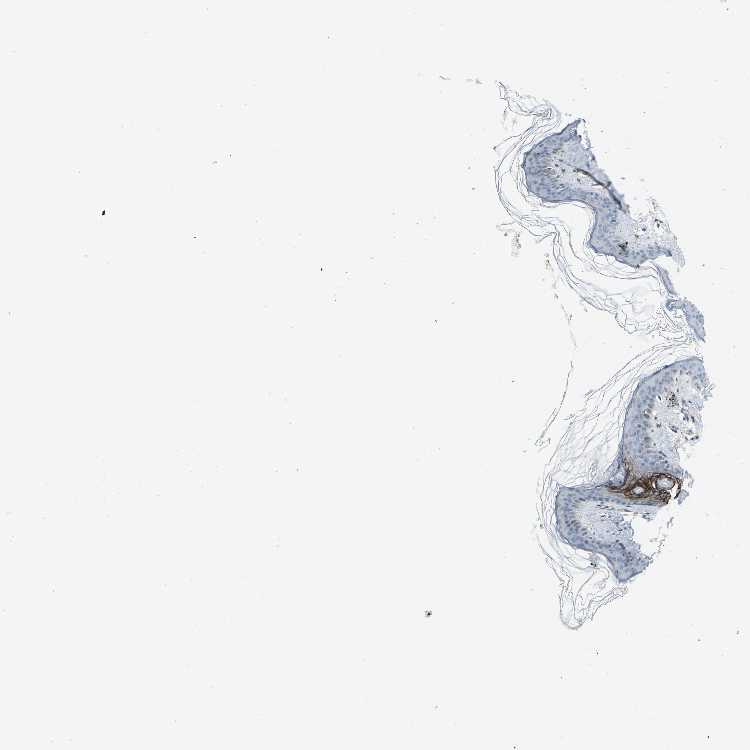

SKIN 1 - Antibody stainingi

Antibody staining in the annotated cell types in the current human tissue is reported as not detected, low, medium, or high, based on conventional immunohistochemistry profiling in selected tissues. This score is based on the combination of the staining intensity and fraction of stained cells.

Each image is clickable and will lead to virtual microscopy that enables deeper exploration of all samples and also displays staining intensity scores, fraction scores and subcellular localization as well as patient and tissue information for each sample.

Antibody CAB013072

Cells in basal layer Not detected

Cells in corneal layer Not detected

Cells in granular layer Not detected

Cells in spinous layer Not detected

Endothelial cells Not detected

Extracellular matrix Low

Fibrohistiocytic cells Not detected

Hair follicles Medium

Langerhans cells Not detected

Lymphocytes Not detected

Melanocytes Not detected

Vascular mural cells Not detected

SKIN 2 - Antibody stainingi

Extracellular matrix Medium